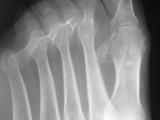

Gout-foot

Gout-foot